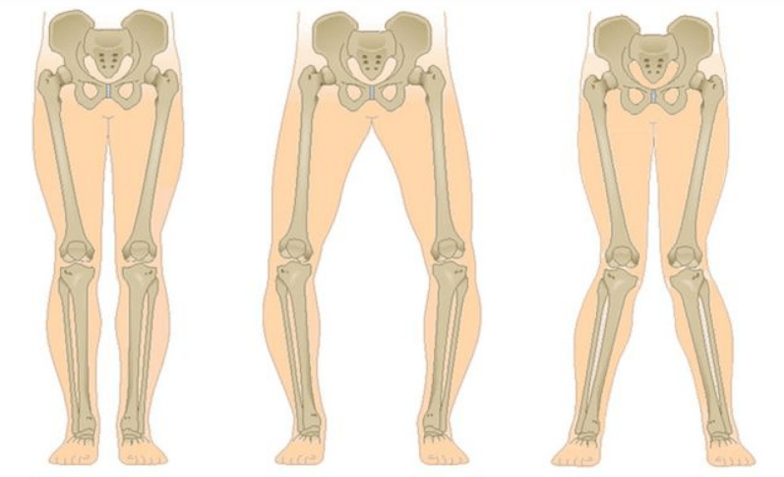

The last stage of gonarthrosis is characterized by the fact that the pain becomes almost constant, causing anxiety not only when walking, but also at rest, and even at night, when patients have to find a comfortable sleeping position.Movement is more limited: it is difficult to fully bend and straighten the leg.The joint becomes deformed and increases in volume.Valgus (X-shaped) or varus (O-shaped) deformity of the legs is often seen.Gait becomes unstable and sways.In severe cases, a cane or crutches are needed.

In osteoarthritis (osteoarthrosis), in addition to the progressive destruction of cartilage, the loss of its elasticity and shock-absorbing properties, the bones gradually become involved in the process.Under load, sharp edges (exostoses) appear, which are mistakenly considered "salt deposits";In classic osteoarthritis, salt deposition does not occur.As osteoarthritis progresses, it continues to "eat away" the cartilage.Then the bone is deformed, cysts form there, all joint structures are affected, and the leg bends.